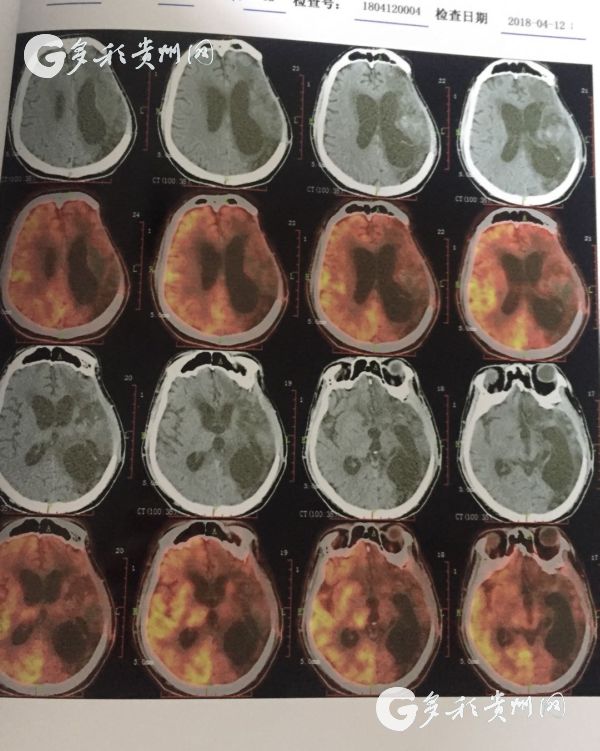

医院提供的患者脑部CT照

据了解,该患者是一位30岁男性,曾因脑出血进行过开颅手术,但术后并发症使病情加重,最后导致长期昏迷,家人最终将其送往beat365正版唯一官网必一附属医院进行治疗。